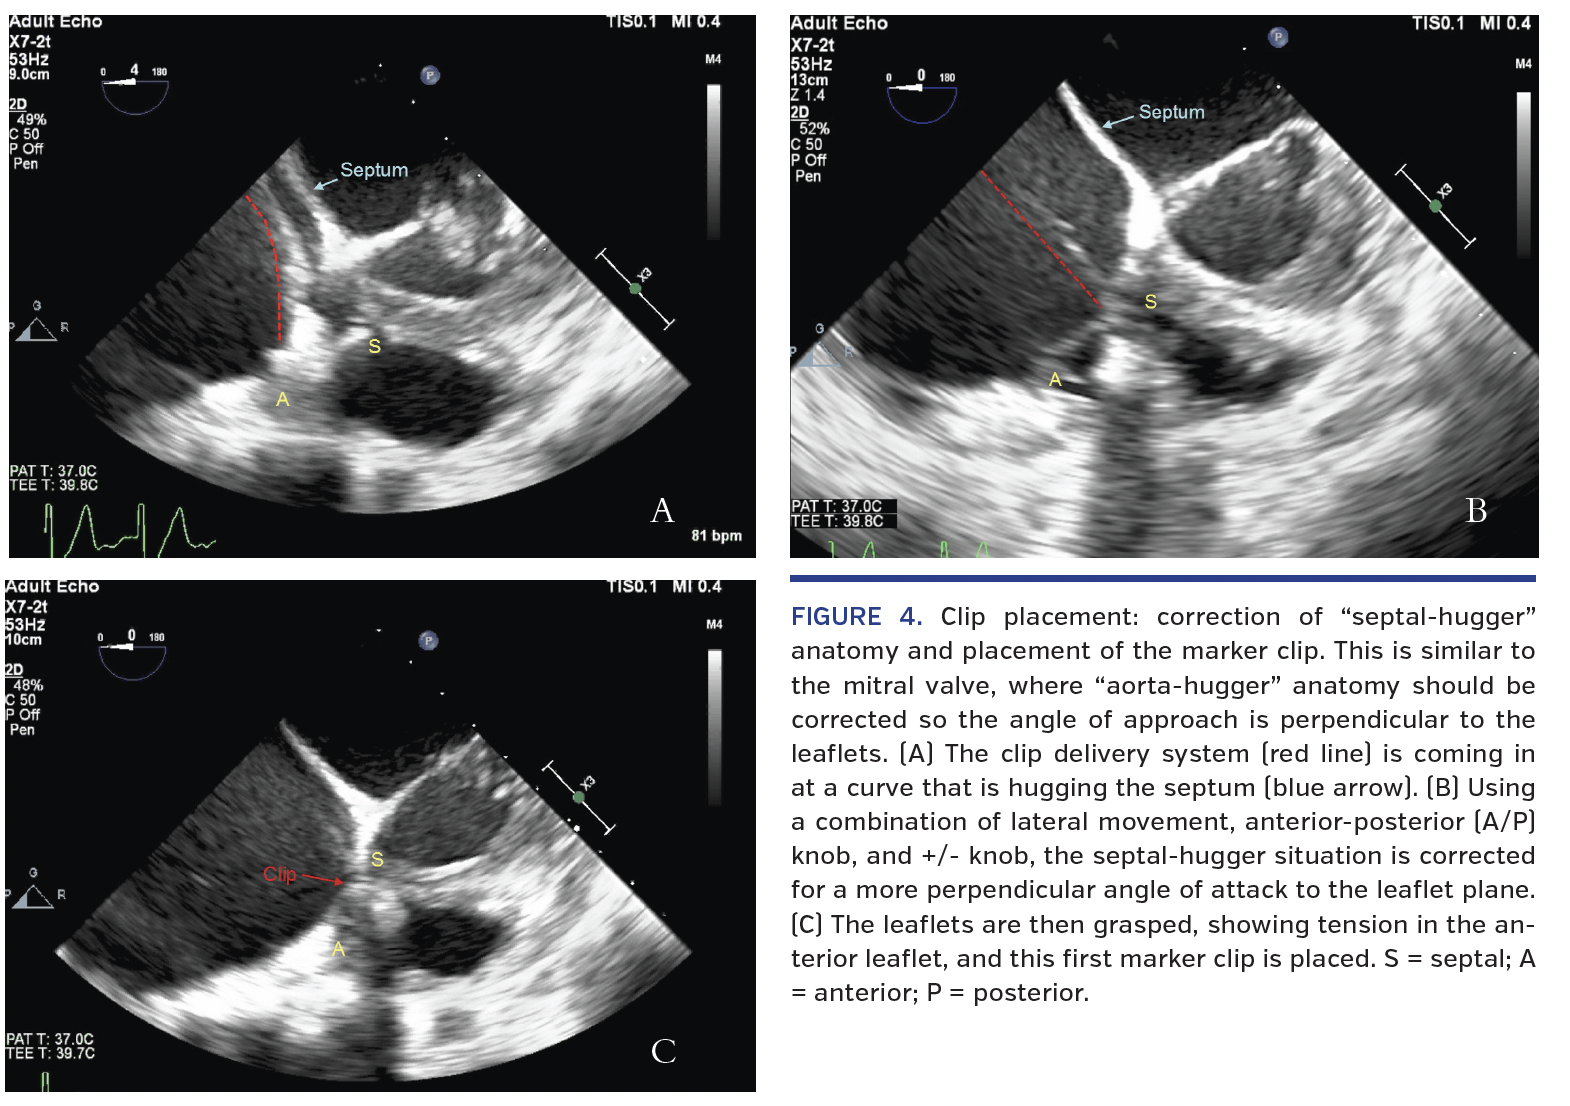

The guide was then positioned using a three-dimensional view from the right atrial perspective, followed by a four-chamber view to show distance from the leaflets (Figure 2). These views indicated there was enough space to advance a clip safely above the leaflets. A clip was then brought outside the guide and opened, followed by rotation to be perpendicular to the chosen coaptation plane (Figure 3). As our goal was to clip the tricuspid valve anterior-septal leaflet coaptation, the mid-esophageal four-chamber TEE view was used. We noted that the guide catheter elbow was abutting against the interatrial septum, termed “septal hugger,” which we corrected in order to make the clip approach perpendicular to the tricuspid valve leaflets (Figure 4). We used a combination of lateral movement of the guide, clockwise or counterclockwise guide catheter

rotation to translate anterior or posterior torque, and use of the device’s anterior-posterior (A/P) and +/- rotating knobs in order to achieve optimal clip position and coaxial approach to the intended valve coaptation plane. We then crossed the tricuspid valve leaflets, assessed again for clip perpendicularity in the TEE subgastric view, and grasped in the mid-esophageal four-chamber TEE view. Leaflet grasp was then evaluated and found to be adequate (Figure 4). As per the accepted standard operating procedures for MitraClip use, we also utilized adjunctive simultaneous fluoroscopy throughout the procedure to ensure appropriate gross directionality of the equipment and to visualize clip opening and closing during grasp preparation.

In this paper, we describe a periprocedural imaging algorithm to facilitate grasping the leaflets of the tricuspid valve using a MitraClip device (Table 1). From an echocardiographic standpoint, the evaluation begins with three-dimensional TEE imaging to understand initial maneuvering to the correct leaflet pair and gross rotation for perpendicularity. The TEE transgastric view is then obtained to evaluate clip position along the commissural-central axis, with use of the “x-plane” to add to the ability to understand perpendicularity. After this, an appropriate two-dimensional view allows fine-tuning of rotation, including correction of a septal hugger guide catheter, as described above in Figure 4. Adjunctive fluoroscopic imaging can be used to show how subsequent clips can relate to the first marker clip location and position. The LAO and AP-RAO views show the clips in two different directions, which can facilitate guide positioning before clip advancement and provide assistance when TEE image acquisition is challenging.